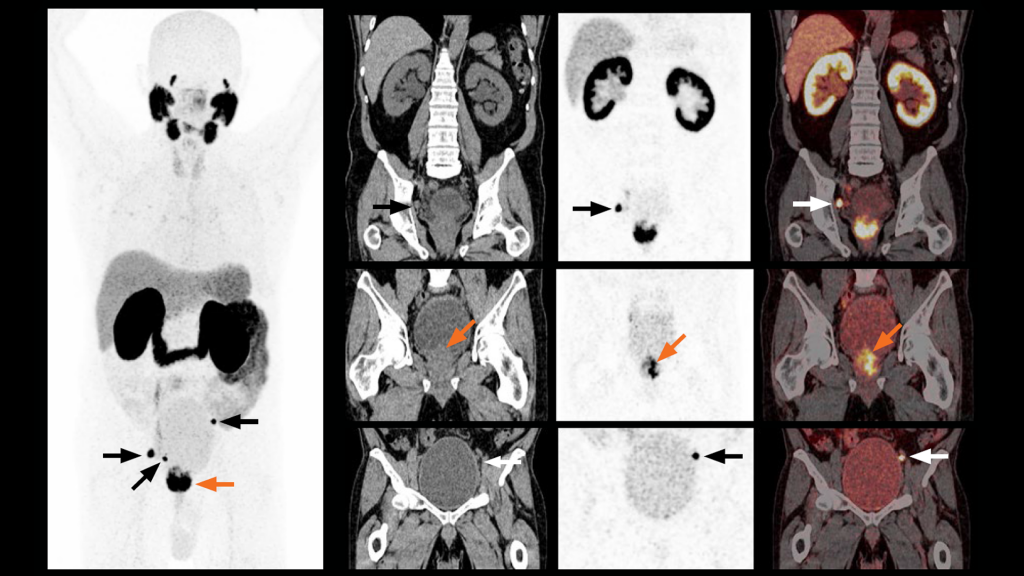

Prostate specific membrane antigen (PSMA) is a molecular glycoprotein which is substantially over expressed in prostate cancer cells. Gallium 68 PSMA PETCT is “one stop shop” best imaging modality for complete staging of prostate cancers useful in planning and reassessing treatment response.

GALLIUM 68 PSMA PET CT